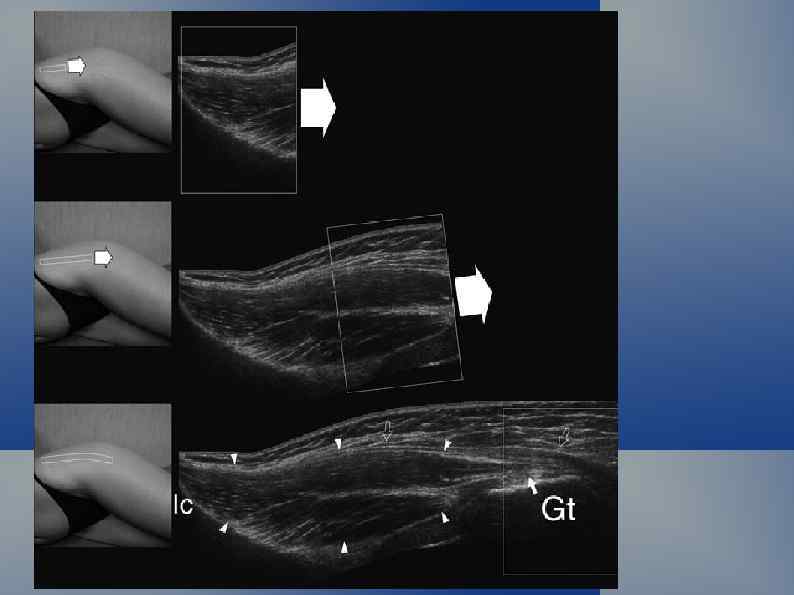

Нормальная ультрасонографическая картина Кожа и подкожная клетчатка

Нормальная ультрасонографическая картина УЗ-сканирование по задней поверхности голени: малая подкожная вена, мелкие подкожные вены, n. suralis